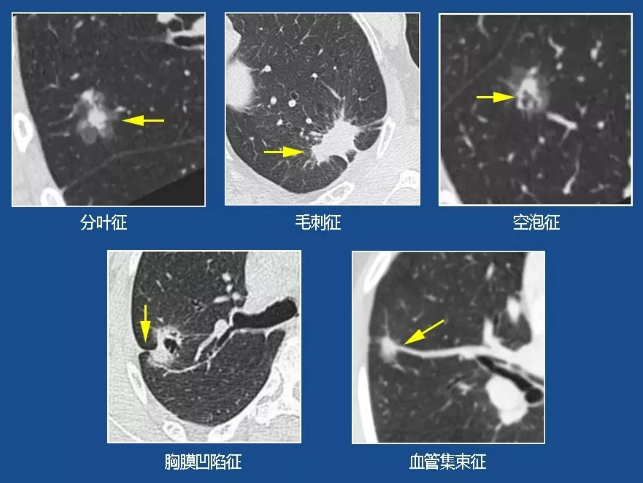

毛刺征,空泡征,胸膜凹陷征及血管集束征,或者在随访观察过程中,有结节